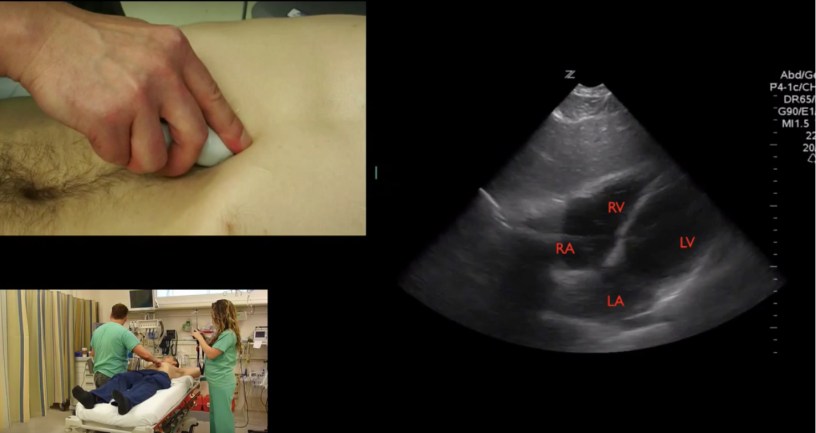

Sono Photo, Sono Stuff #POCUS #Cardiac #Anatomy in a subxiphoid view with probe placement. #foamed #foamus #meded Date: July 22, 2016Author: Mike 0 Comments Share this: Share on X (Opens in new window) X Share on Facebook (Opens in new window) Facebook Like Loading...